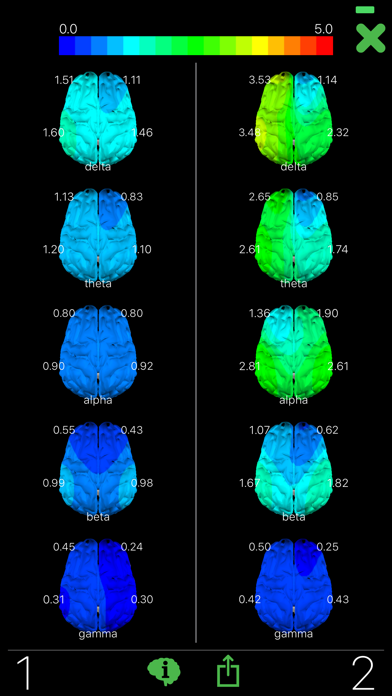

Have you ever wondered what your brain looks like? Opti Brain allows you to map your brain activity with the help of Muse, the brain sensing headband. Collect and save your brain data from your brain sensing hardware. Name and assign a quality to your collections to categorize and remember them. Then create and compare maps and movies of your brain activity. Opti brain also provide interpretations with each map you create.

The Opti Brain app is brought to you by Opti Brain, a company dedicated to helping you optimize your performance. Record your brain data during different activities (resting; critical thinking; before, during and after performance based sports and activities; etc.) and compare the patterns in your brain maps. Discover your BETTER THAN BEST™ brain pattern when you are performing at your full potential!

Have you ever wondered what your brain looks like? Opti Brain allows you to map your brain activity with the help of Muse, the brain sensing headband. Collect and save your brain data from your brain sensing hardware. Name and assign a quality to your collections to categorize and remember them. Then create and compare maps and movies of your brain activity. Opti brain also provide interpretations with each map you create.

The Opti Brain app is brought to you by Opti Brain, a company dedicated to helping you optimize your performance. Record your brain data during different activities (resting; critical thinking; before, during and after performance based sports and activities; etc.) and compare the patterns in your brain maps. Discover your BETTER THAN BEST™ brain pattern when you are performing at your full potential!